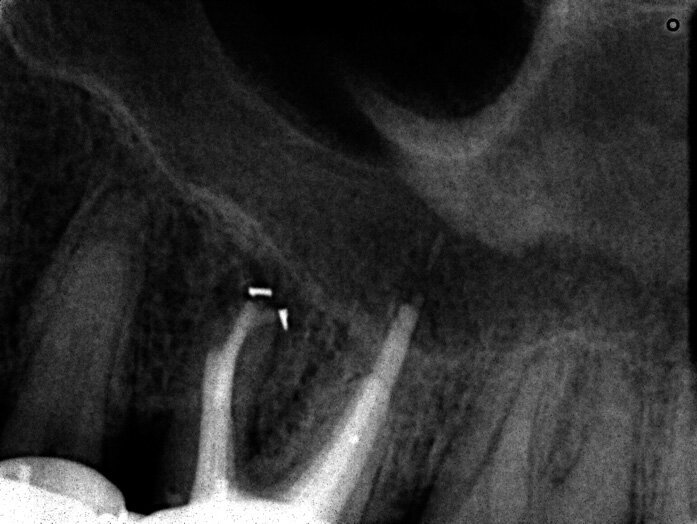

Un patient avait été adressé au cabinet en raison de problèmes associés à la fracture d’une lime. Il était pilote de ligne et se plaignait d’écoulements nasaux purulents lorsqu’il était en vol. La radiographie pré-opératoire (Fig. 1) a distinctement montré la présence de deux fragments d’une lime fracturée dans les canaux mésiaux et d’un cône traversant l’apex de la racine palatine. Après l’imagerie CBCT avec iCAT, il est apparu clairement que le sinus gauche était presque totalement rempli de liquide inflammatoire (Fig. 2) et que le cône présent dans le canal palatin pénétrait dans le sinus. Sur l’image de reconstruction multi planaire (MPR), nous pouvions également distinguer les deux fragments de lime fracturée dans les deux canaux mésiaux (Figs. 3 et 4) et aussi un autre fragment dans le sinus sans aucun contact avec le canal (Fig. 5). L’utilisation de différents filtres nous a permis de visualiser les fragments de lime (Figs. 6–9), ainsi que l’inflammation et le fragment de lime fracturée à l’intérieur du sinus. Nous avons également mieux perçu la position du cône qui émergeait du canal palatin et pénétrait dans le sinus.